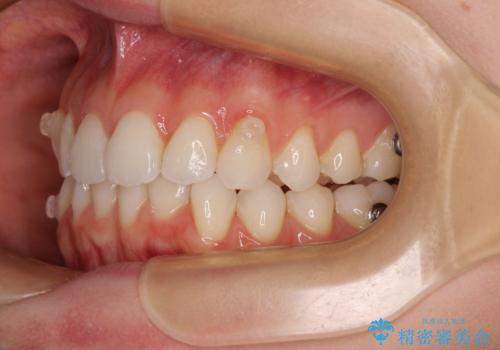

前歯のデコボコと深い咬み合わせ インビザラインできれいに改善

- 前歯のデコボコと下の前歯が隠れてしまう咬み合わせを気にして来院された患者様です。

インビザラインによる上下歯列の拡大と、IPR(歯と歯の間を削る)にるスペースの獲得により、口元のデコボコとディープバイトを改善することとしました。

インビザラインは、装着していない時間がどれだけ短いかが、治療期間を大きく左右します。こちらの患者様は1日22時間以上、毎日欠かさず装着してくださったため、1年弱という短期間で満足のいく歯列に整えることができました。